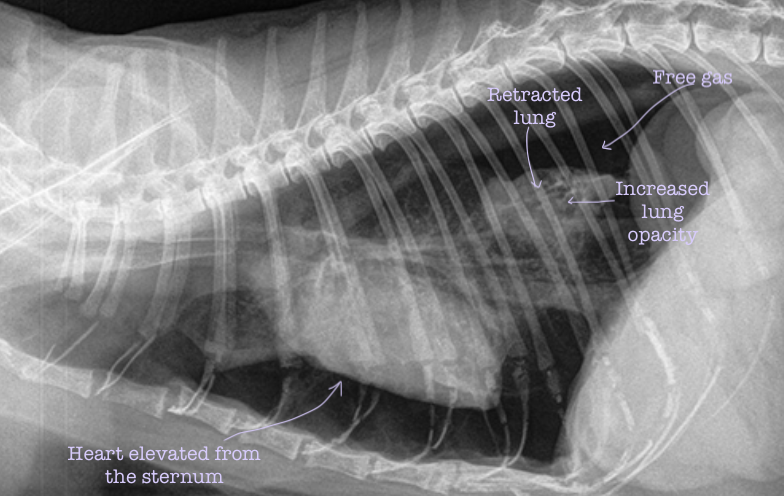

What are the three characteristic signs of a pneumothorax on a radiograph?

Heart elevated from the sternum Retraction of the lung lobes with free gas between the lung and the thoracic wall

Increased lung opacity

What are the five characteristic signs of a tension pneumothorax on a radiograph?

Heart always elevated from the sternum

Retraction of the lung lobes with free gas between the lung and the thoracic wall

Flat or concave diaphragm

Increased size of intercostal spaces